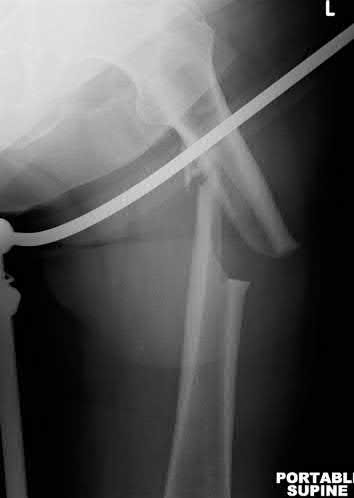

A 15-year-old boy presents with a permeative lytic lesion in the femoral diaphysis with aggressive periosteal reaction ('onion skinning'). Biopsy reveals uniform small round blue cells. Cytogenetic analysis of this tumor will most likely demonstrate which of the following translocations?

Explanation

The clinical and radiographic description is classic for Ewing sarcoma. The characteristic cytogenetic abnormality is a balanced translocation t(11;22)(q24;q12), which fuses the EWS gene on chromosome 22 with the FLI1 gene on chromosome 11. This is seen in approximately 85-90% of Ewing sarcomas. t(9;22) is the Philadelphia chromosome (CML), t(X;18) is seen in synovial sarcoma, t(2;13) in alveolar rhabdomyosarcoma, and t(12;16) in myxoid liposarcoma.